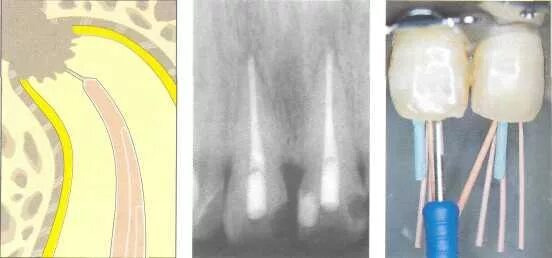

Ретроградное пломбирование корневых